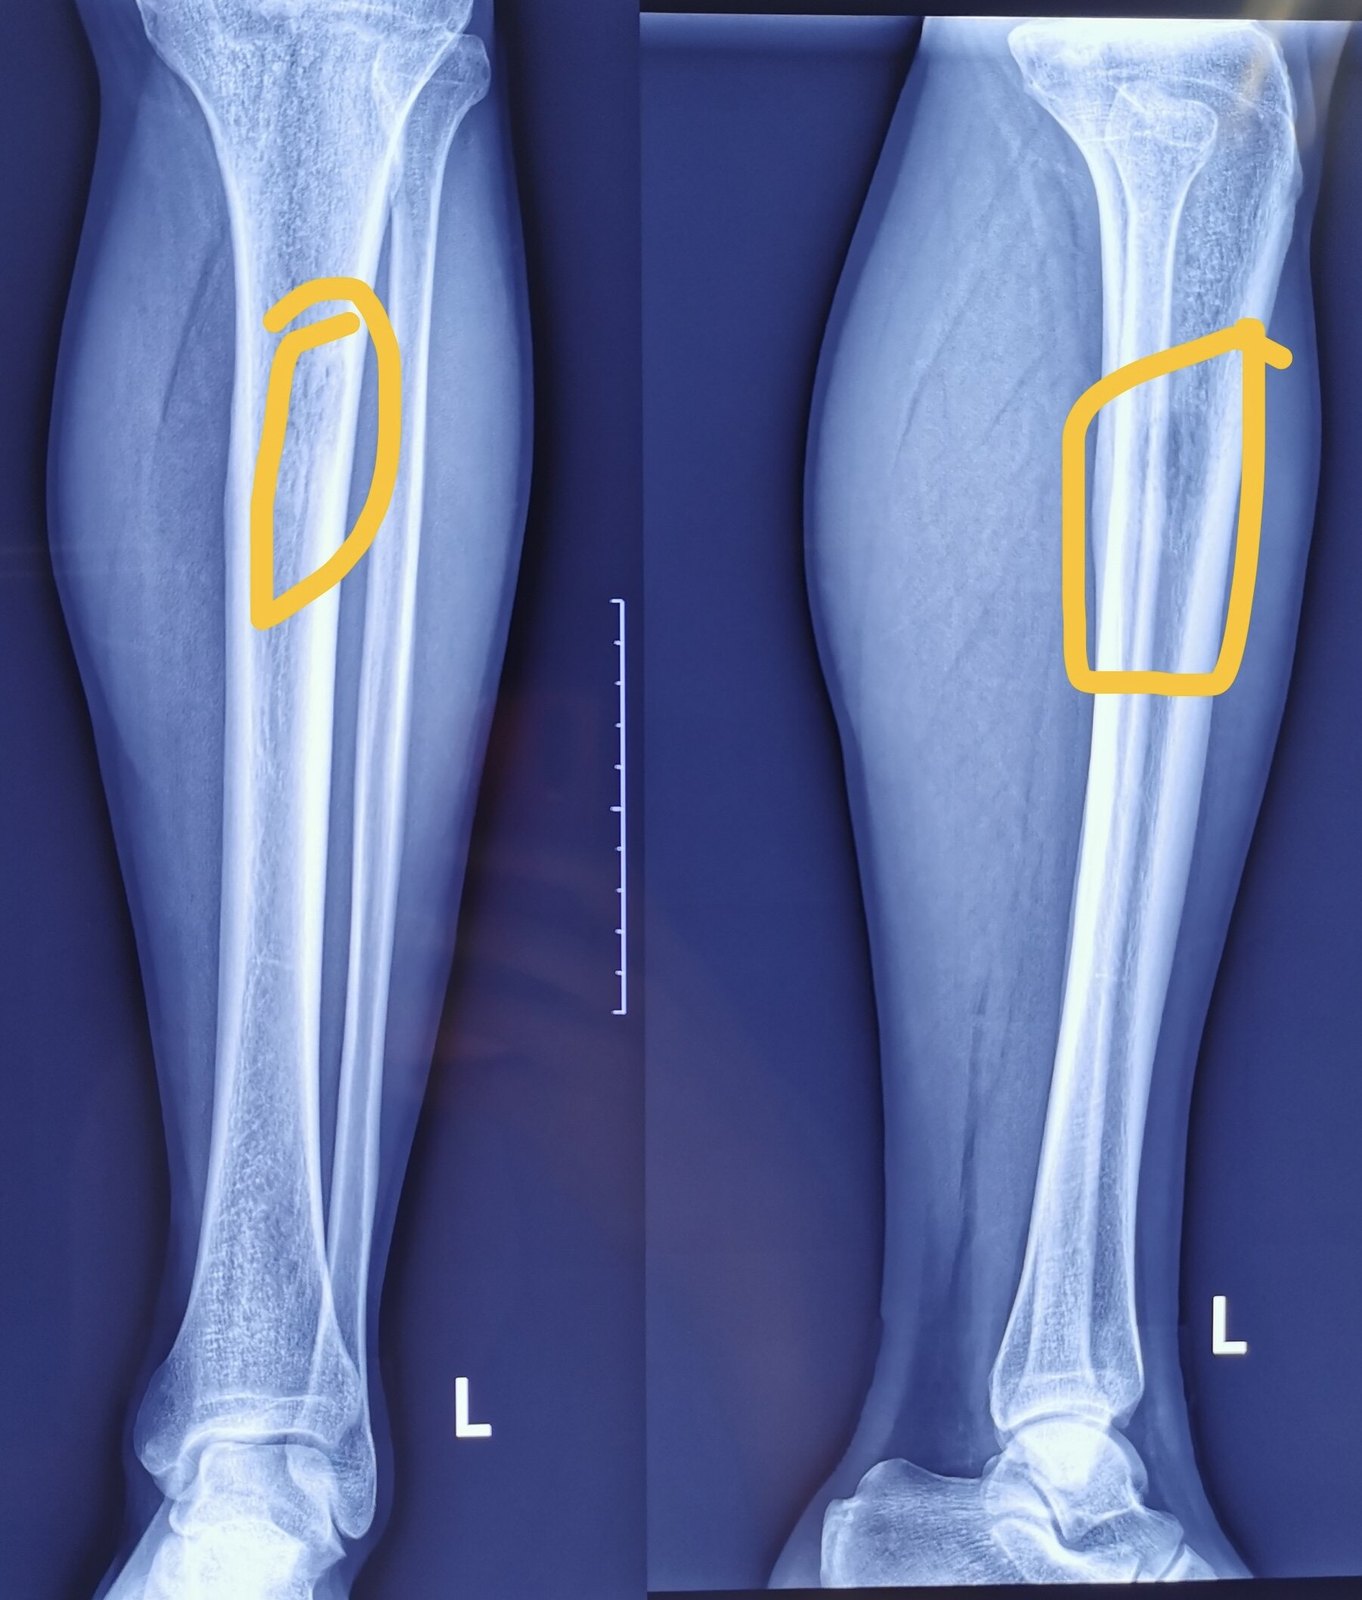

1).四肢良性骨肿瘤的随访主要涉及肿瘤是否复发?一般而言,四肢良性骨肿瘤手术切除或者切刮后复发率很低,但骨骼由于其特殊的支撑作用和生物学结构,有时候肉眼和X线透视难以判断手术是否切除完全?只能通过动态观察、追踪,做术前、术后的连续性对照观察。比如术区逐渐出现的透亮影、不规则间隙等,随访是变大、变小、变模糊?对照术前和手术中情况、结合年龄做出分析和判断。

4.在随访中出现的骨膜反应需要区别对待,之前有骨折或者病理性骨折的,手术后骨愈合过程中出现的骨膜反应无须恐慌!